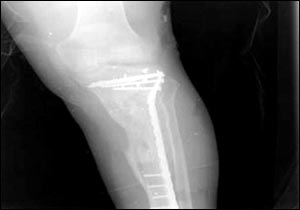

烏代傷腿的X光照片

7月24日,美國(guó)國(guó)防部通過(guò)由美國(guó)資助的伊拉克電視臺(tái)、兩家阿拉伯衛(wèi)星電視臺(tái)以及美國(guó)本土的CNN(有線新聞網(wǎng)絡(luò))將薩達(dá)姆的兩個(gè)兒子烏代和庫(kù)賽遭美軍擊斃慘死的照片公諸于世,同時(shí)被曝光的還有1996年烏代遇刺后所拍的傷腿的X光片。據(jù)悉,近60的伊拉克人收看這檔節(jié)目。此前,美軍中央司令部的里卡多·桑切斯中將在巴格達(dá)舉行新聞發(fā)布會(huì)時(shí)說(shuō),判斷烏代和庫(kù)賽被打死的依據(jù)是在現(xiàn)場(chǎng)發(fā)現(xiàn)的牙齒以及曾任薩達(dá)姆助手的目擊證人的指認(rèn)。